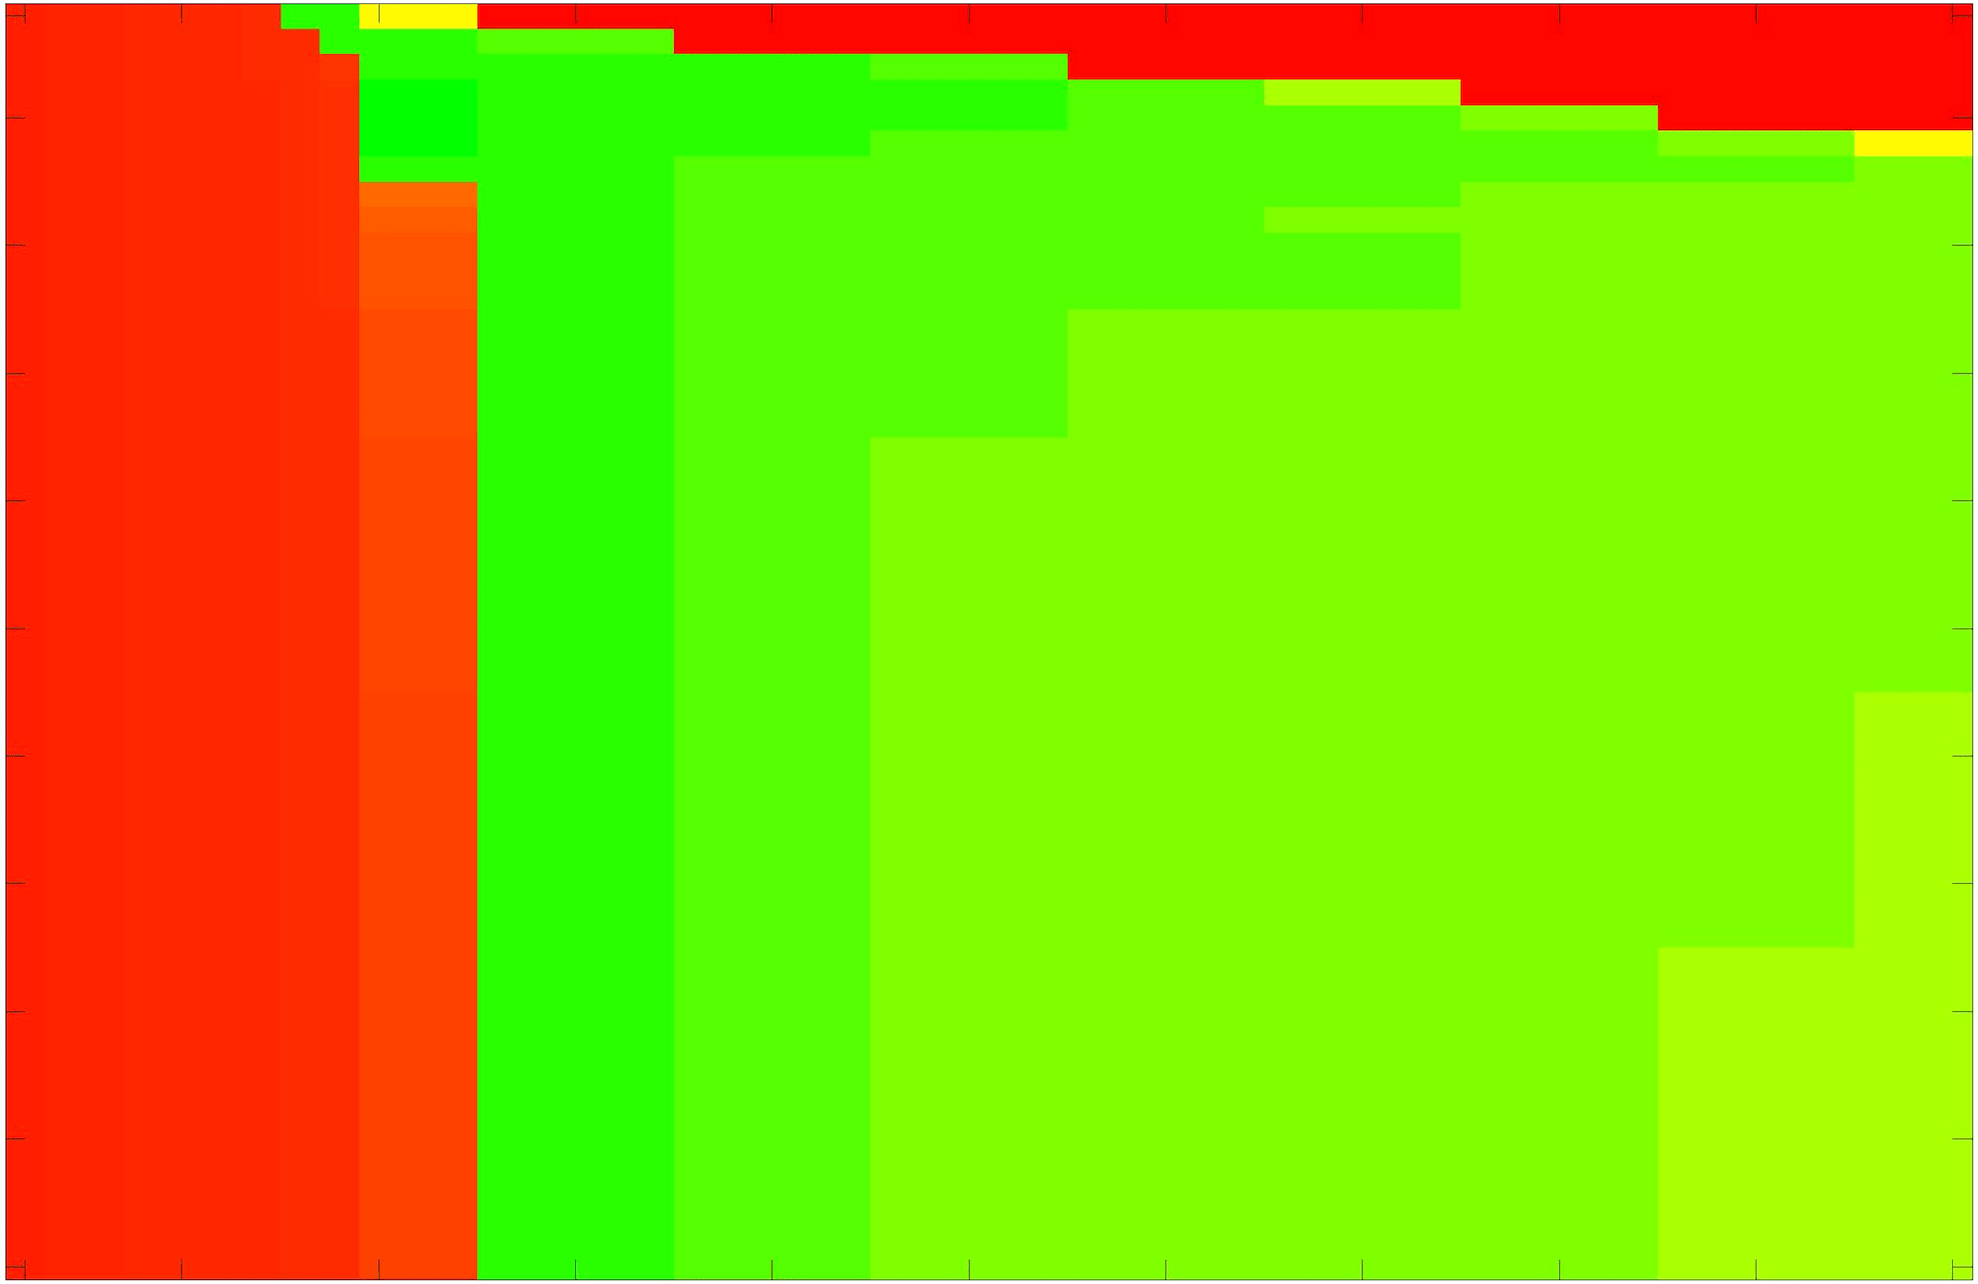

In these tests we aim to demonstrate how sensitive to parameter choices each choice of fitting term is. To accomplish this we perform the segmentations for each of the models discussed (CV, RSF, LCV, HYB, GAV) and the proposed model for a wide range of parameters and compute the TC value. The parameter range used is . Due to computational constraints, we run for each integer between 1 and 10, and every fifth from 15 to 50. This aspect of a model’s performance is vital when used in practice. The less sensitive to parameter choices a model is the more relevant it is in relation to potential applications. It should be noted that we neglect to test the selective models detailed in §3 with respect to parameter robustness as we are using the authors’ implementation of each approach. Instead, we make direct comparisons in the following sections.

The TC values for the parameter sets are presented as heatmaps in Figs. 11–13. A heatmap is a convenient way to display accuracy results for hundreds of tests concisely. In Fig. 9 we give an example heatmap with the same axes used for those in Figs. 11–13. For each of the combinations of parameter values we give the TC value of the segmentation result and represent it by the appropriate colour. The corresponding colour scale is shown in Fig. 8. Qualitatively, the more green areas of the heatmap the more accurate the model is for a wider set of parameters. Example results for Test Image 5 when varying (with ) for the proposed model are given in Fig. 10. Here it can be seen what each accuracy result corresponds to visually.

Note. The axes have been removed from the heatmaps in Figs. 11–13 for presentational clarity. However, to be explicit, the axes used in all heatmaps are the same as those in Fig. 9.

Real Images. In Fig 12 we present results for Test Images 4–6. Here, the proposed model performs in a similar way to its competitors because these images are more typical selective segmentation problems in the sense that there is a clear distinction between the foreground and background intensities. In particular, the values in each case are: Test Image 4 , Test Image 5 , and Test Image 6 . It can be seen that the proposed model is competitive compared to previous approaches. The performance is quite poor for Test Image 5, but is arguably still the best for this challenging case. In Fig. 13 we present results for Test Images 7–9. Here the proposed model outperforms previous approaches significantly for each image. This is mainly due to the type of image considered. Specifically, the true intensities are: Test Image 7 , Test Image 8 , and Test Image 9 . The proposed model is capable of achieving results where , with other models failing completely in these cases.